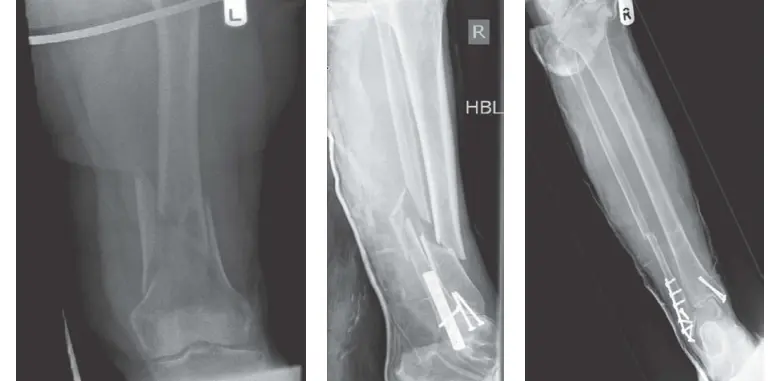

- الأشعة السينية (X-rays): هي الفحص الأولي والأكثر شيوعًا لتأكيد وجود الكسر وتحديد موقعه ونوعه العام. يتم أخذ صور من زوايا متعددة (عادة أمامية وجانبية) للحصول على رؤية ثلاثية الأبعاد للكسر.

- التصوير المقطعي المحوسب (CT Scan): لا غنى عنه في الكسور المعقدة. يوفر صورًا مقطعية مفصلة للعظم، ويسمح بإنشاء نماذج ثلاثية الأبعاد (3D reconstruction) للكسر. هذا يساعد الأستاذ الدكتور محمد هطيف على فهم دقيق لعدد الشظايا، مدى تفتت الكسر، ومدى امتداد الكسر إلى المفاصل، مما يسهل تخطيط الجراحة بدقة متناهية.

- يتم تثبيت العظم باستخدام صفائح معدنية (plates) ومسامير (screws) خاصة، أو أسلاك (K-wires)، أو براغي (screws) منفردة. يتم اختيار نوع التثبيت بناءً على نوع الكسر ومكانه.

المسامير النخاعية (Intramedullary Nailing):

- تُستخدم بشكل خاص لكسور العظام الطويلة مثل عظم الفخذ والقصبة.

- يتم إدخال قضيب معدني طويل (مسمار) داخل القناة النخاعية للعظم عبر شق صغير، ثم يتم تثبيته بمسامير في الأعلى والأسفل.

- هذه التقنية توفر تثبيتًا قويًا وتسمح بحمل الوزن المبكر في بعض الحالات.

- الصفائح والمسامير (Plates and Screws): تُوضع صفائح معدنية خاصة على طول العظم أو عبره، وتُثبت بمسامير تخترق العظم لتثبيت الشظايا بإحكام. يختار الدكتور هطيف نوع الصفائح والمسامير (مثل الصفائح القفلية Locking Plates) التي توفر أقوى تثبيت وأفضل نتائج.

- المسامير النخاعية (Intramedullary Nails): في كسور العظام الطويلة، يتم إدخال مسمار داخل القناة النخاعية للعظم، ثم يُثبت بمسامير قفلية من الطرفين.